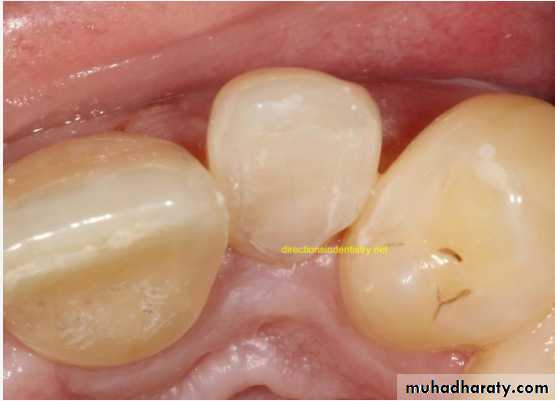

Gemination (twining):

*Gemination is a rare anomaly that arises when the tooth bud of a single tooth attempts to divide.

The result may be an invagination of the crown, with

partial division, or in rare cases complete division

throughout the crown and root, producing identical

structures. Complete twinning results in a normal tooth

plus a supernumerary tooth in the arch.

*The patient has a larger tooth but a normal number of teeth overall, in contrast to fusion, where the patient would appear to be missing one tooth.

• Fusion of the left mandibular central and lateral incisors (twoindividual roots, two root canals and two joined crowns).

Gemination of right mandibular central incisor has one root, one root canal and a partially bifid dental crown.